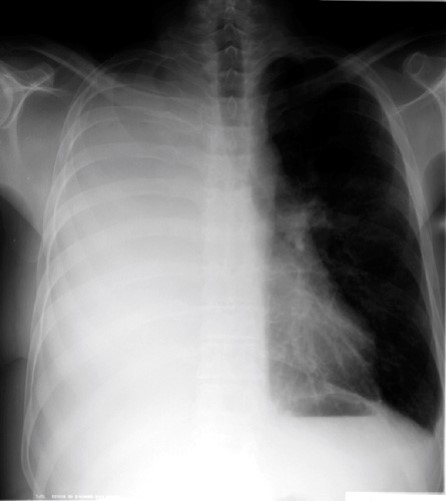

38yo male with dyspnea and pleuritic chest pain for a week

View: PA

DX: cavitary lesion associated with community acquired MRSA